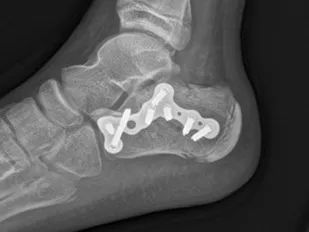

术后外观照 术后X光照片

该患儿因高处坠落导致双侧跟骨粉碎性骨折,骨折移位明显且累及距下关节面,手术指征明确。考虑到患儿年龄较小,传统开放手术创伤大、出血多且可能影响骨骼生长发育,骨科一区团队经充分讨论后,决定采用微创的经跗骨窦小切口入路方式进行治疗。手术由张鹏主治医师和余靖住院医师共同实施。两位医师凭借精湛的医术和默契的配合,通过经跗骨窦小切口精准地对骨折部位进行了复位和固定。手术时间短,失血量少,最大限度地降低了手术风险和对患儿的创伤,充分体现了微创手术的优势。术后,在医护人员的精心护理下,患儿伤口一期愈合,未出现伤口积液、感染等并发症。经过5天的观察与治疗,患儿身体状况恢复良好,顺利出院。此次微创手术的成功实施,充分展示了连州市人民医院骨科一区在微创治疗领域的精湛技艺和专业素养。